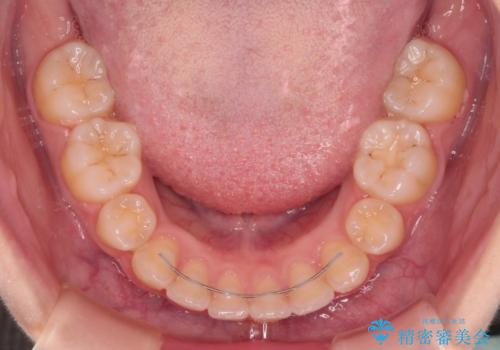

口が閉じられない ワイヤー装置での抜歯矯正

- 上下の前歯が突出しており、口が閉じにくいとのことで来院された患者様です。

上下前歯が著しく前突している状態であったので、上下左右の第1小臼歯4本を抜歯し、ワイヤー装置にて矯正治療を行うこととしました。

舌の突出癖により、前突になったと考えられたため、舌のトレーニングをしっかりと行うよう指導しました。

舌の突出癖があり、前歯の移動量も多くなるため、治療期間は長くなると予想されましたが、13ヶ月という予定の半分程度の期間で終えることができました。